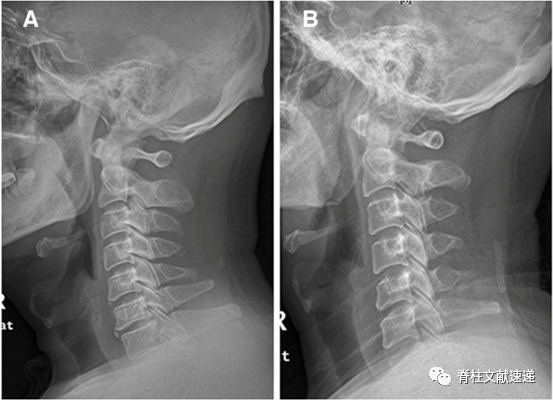

文献三

该文献进一步指出了项韧带骨化和OPLL的相关性,并举出3个病例,如下图。